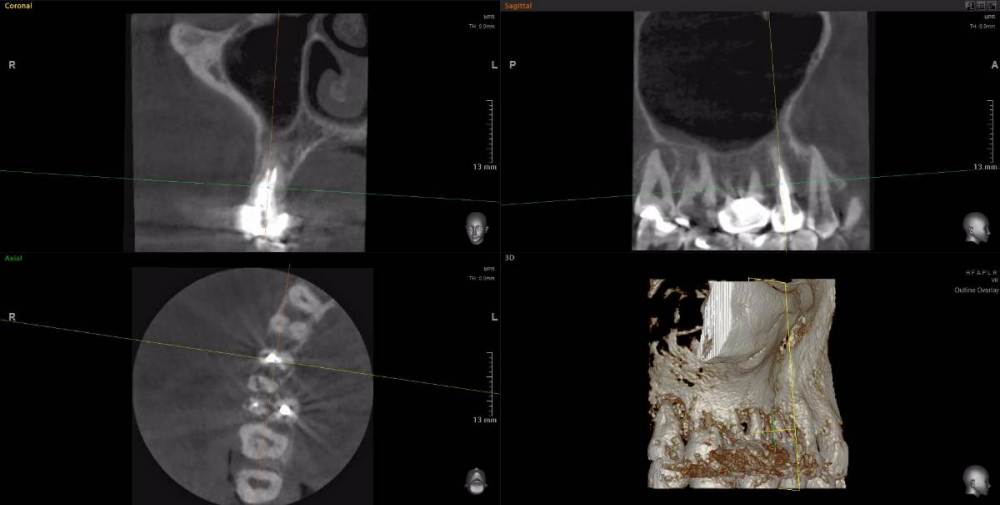

Рабин Опубликовано 18 мая, 2021 Автор Поделиться Опубликовано 18 мая, 2021 Добрый день! Сделала КТ этого зуба, как вы просили... https://cloud.mail.ru/stock/kkbze24nzBzfEqnUbdPwtsei Видите ли вы воспаление на нём и можно ли его спасти? Интересует также соседний 15 зуб. Спасибо! Ссылка на комментарий

wladdX Опубликовано 18 мая, 2021 Поделиться Опубликовано 18 мая, 2021 (изменено) Зуб 16, на мой взгляд, придётся удалить. Зуб 18 тоже Зуб 15 вроде бы и не вызывает особых восторгов, но и явного неприятия тоже. Изменено 18 мая, 2021 пользователем wladdX 2 Ссылка на комментарий

red_butler Опубликовано 20 мая, 2021 Поделиться Опубликовано 20 мая, 2021 18.05.2021 в 23:24, wladdX сказал: Зуб 16, на мой взгляд, придётся удалить. +1 Ссылка на комментарий

wladdX Опубликовано 29 мая, 2021 Поделиться Опубликовано 29 мая, 2021 18 - там приличных размеров корневая гранулёма, излечить нереально 1 Ссылка на комментарий